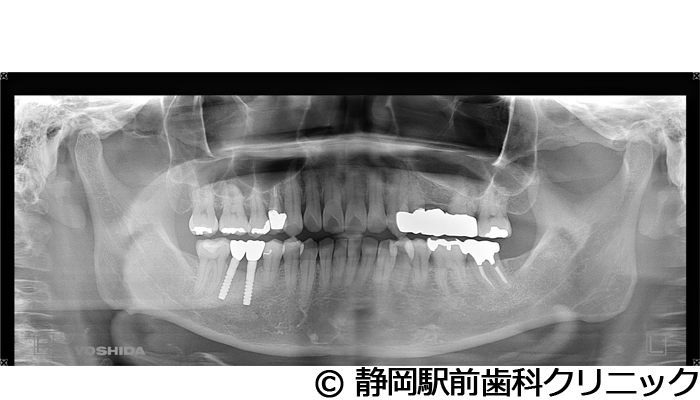

【症例3】右下インプラント埋入

- 治療前

- 治療後

- 治療名

- 右下インプラント埋入

- 費用

- 440,000円(税込)

- 期間

- 6ヵ月

治療内容

患者様の症状

右下の歯が折れてしまい、食べにくいため、インプラント治療希望。

治療方法

右下2本は抜歯を行い、骨の治癒後にCTを撮影し、詳細に治療計画を立案しました。その後、インプラントを埋入し、人工歯を被せて咬合の回復を行いました。

治療結果

患者様からは右でも好きな物を食べることができるようになり、喜んでいただきました。人工歯はセラミックにて作成し、見た目もご満足いただけました。

※治療結果は個人差があります。

治療を行う上での注意点(リスク・副作用)

術後は、出血、腫れ、痛みなどが出る可能性があります。